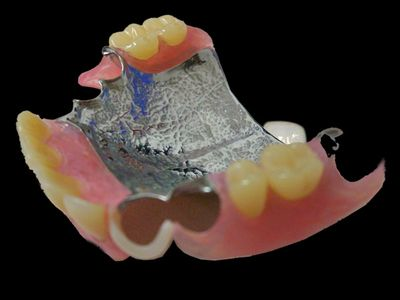

入れ歯治療

入れ歯は個人により、適切な形態が異なり ます。患者様一人一人に合った入れ歯を提案します。

保険適応の義歯が基本ですが、ご希望により

金属床

ノンクラスプデンチャー

の製作も行っています